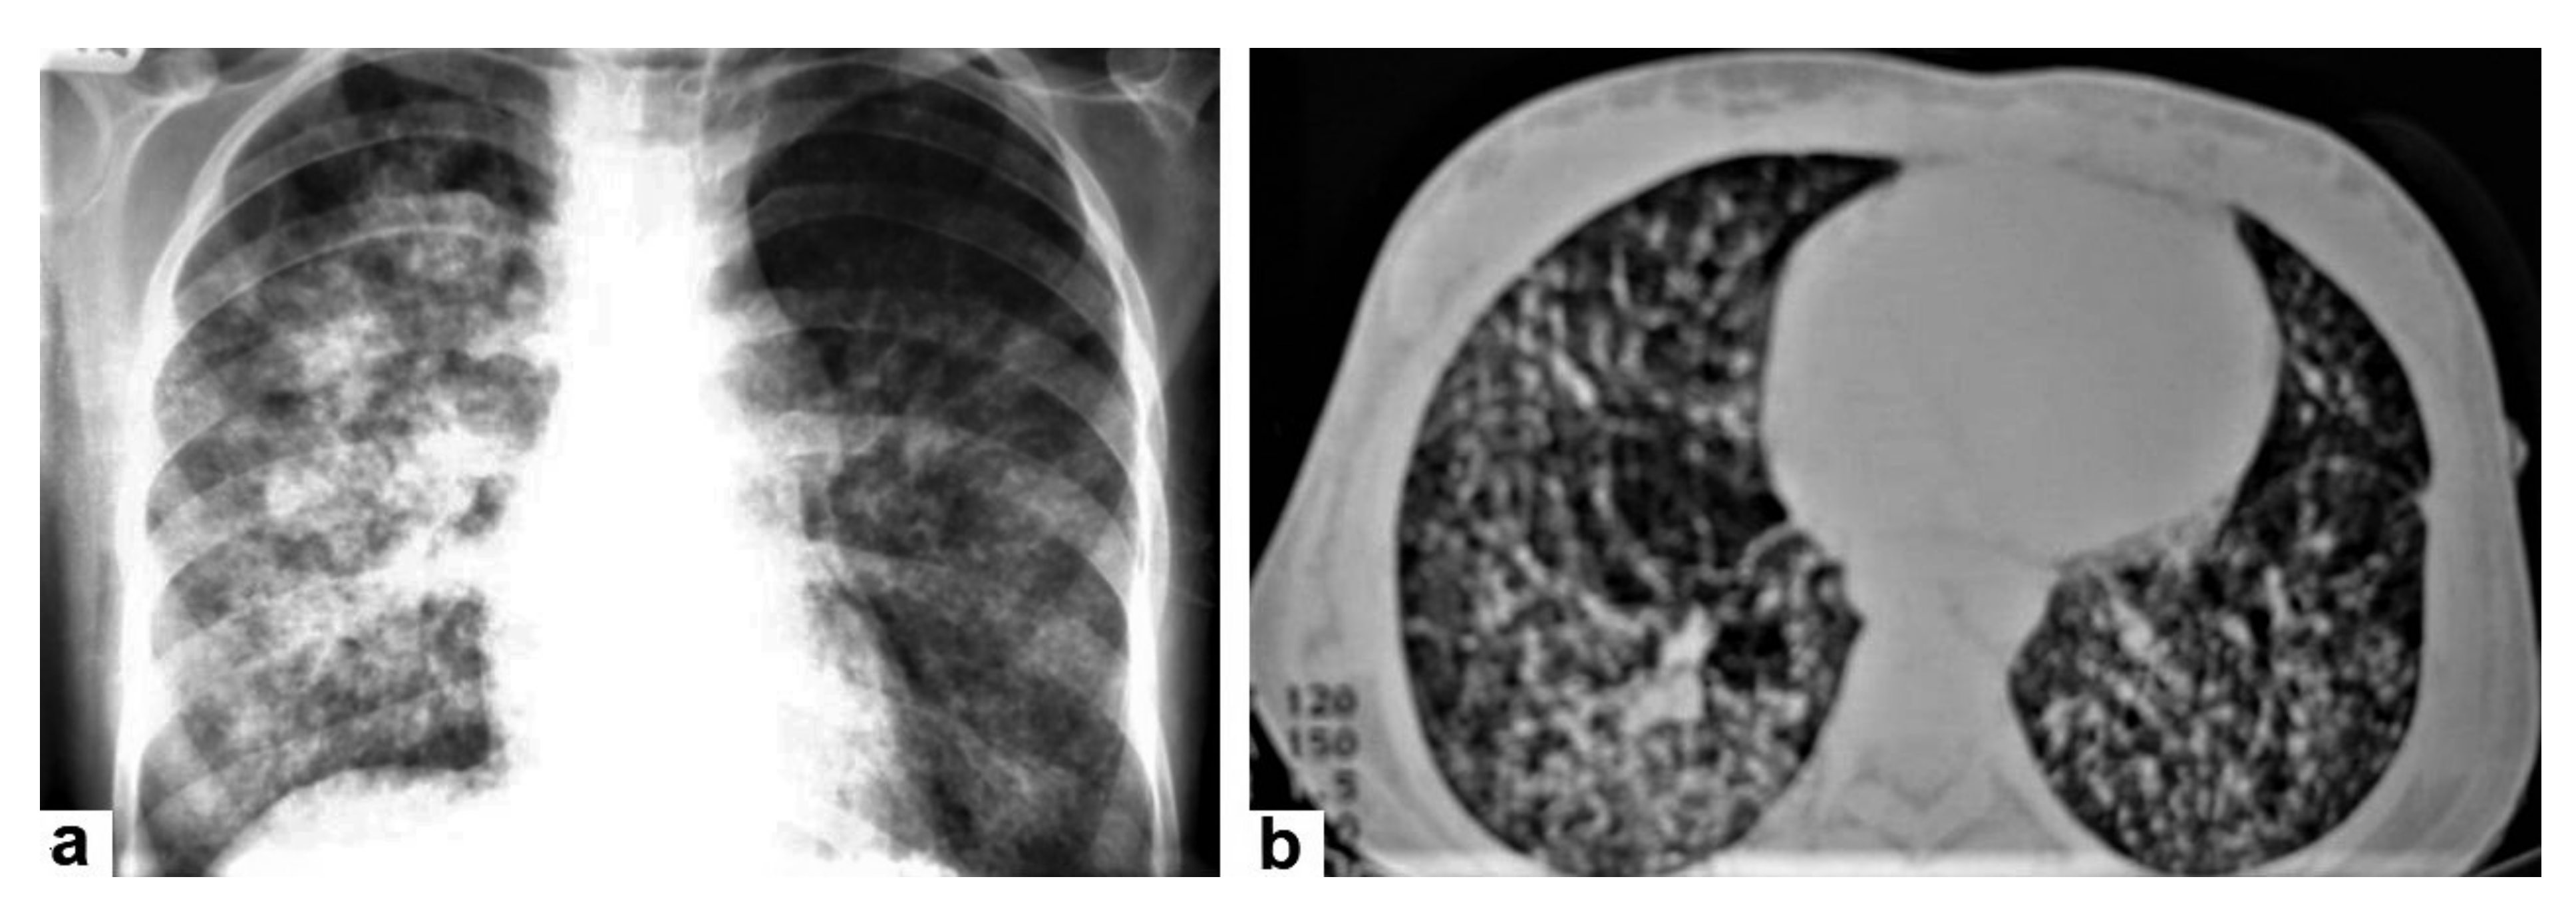

• Miliary TB (Figure 6 and Figure 7) appears as innumerable small (1–3 mm) granulomas with random distribution in the lungs and other organs with a predominance to the lung bases due to the gravity-dependent high blood flow. It occurs due to the hematogenous dissemination of mycobacterium tuberculosis bacilli, especially in immunocompromised patients and children [1,13]. Miliary TB is a significant differential diagnosis of pulmonary metastasis from thyroid cancer or others, even in children [19].

Figure 6. Miliary TB in an 18-year-old man (same patient of Figure 1). (a) Chest radiograph shows superimposed innumerable small nodules in lungs right greater than the left predominantly affecting lung bases due to gravity-dependent high blood flow. (b) Axial chest CT shows innumerable small (1–3 mm) nodules with random distribution in both lung fields.